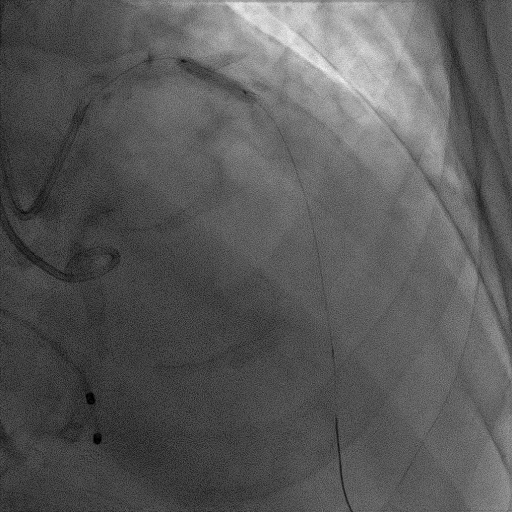

造影提示微少量返流,压力监测提示主动脉瓣压差7mmHg

手术过程

患者麻醉方式为全麻,建立静脉通路后,穿刺右侧股静脉,预埋ProGlide缝合器,食道超声指导下房间隔穿刺成功,将Superstiff导丝送至左房,应用18F鞘管扩张穿刺部位,沿导丝将导引导管送入左房,MitraClip调整后顺利到达二尖瓣目标位置,在X线及食道超声辅助下,将Mitraclip NTR成形夹精确定位后,成功夹合二尖瓣A2-P2区,超声显示反流明显减少,多切面证实夹合组织充分,肺静脉多普勒波形由反向恢复正常,手术顺利结束,安返普通病房。